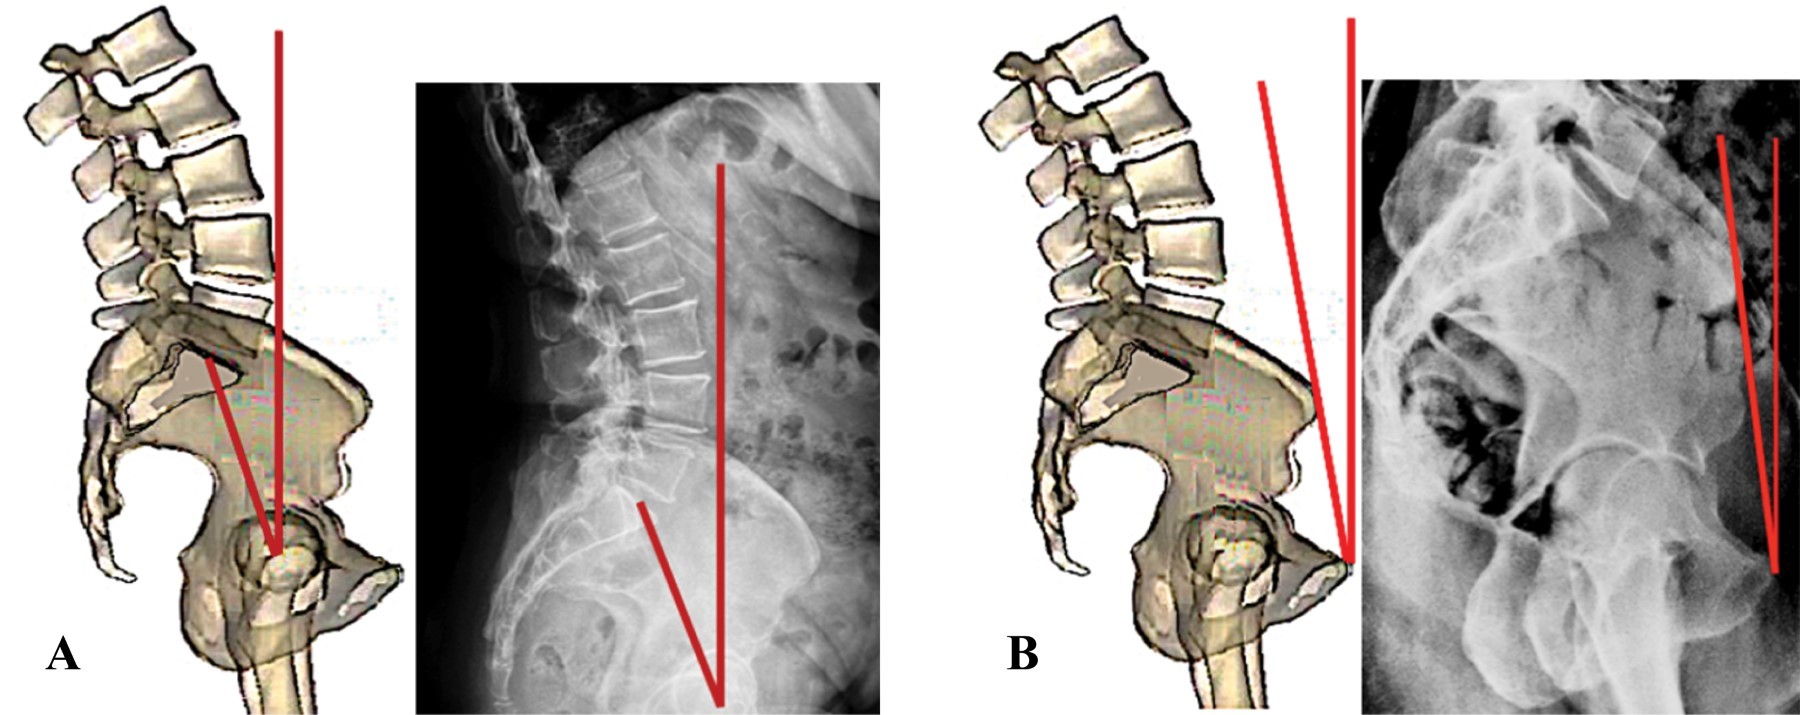

Inclinación pélvica (pelvis tilt). La definición de "pelvis tilt" está sujeta a una seria controversia. Los cirujanos de columna definen al "pelvis tilt" como el ángulo que forman el plano coronal y una línea dibujada desde el centro de las cabezas femorales (eje bicoxofemoral) al punto medio de la plataforma sacra (Figura 14A). Esta definición es útil en cirugía de columna, ya que se emplea para estudiar el balance sagital global atendiendo principalmente los centros de gravedad, tanto en columnas normales como patológicas. Lo anterior es de escasa utilidad en cirugía artroplástica de cadera cuando se estudia la posibilidad de luxación.

En cirugía de cadera se prefiere definir a la inclinación pélvica (pelvis tilt) tomando en cuenta la positividad o negatividad del ángulo formado entre plano anterior de la pelvis y la línea del plano coronal (Figura 14B). La razón de utilizar esta última definición es porque el interés de un cirujano artroplástico de cadera es la correcta colocación del componente protésico acetabular. Es importante considerarla ya que sabemos que la rotación pélvica modifica la anteversión acetabular.

Figura 14